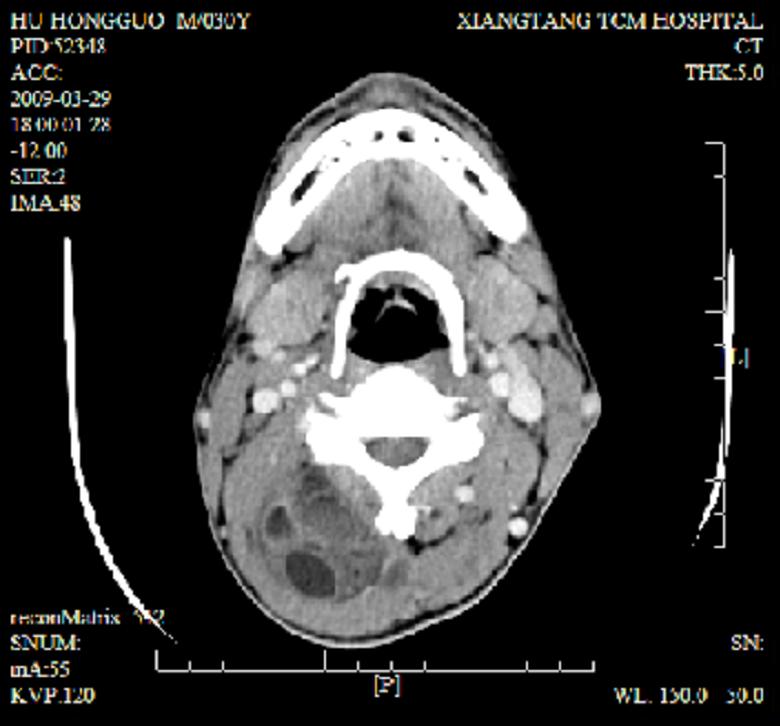

标题: CT19102:颈部肿块

男30y发现肿块3年

多处囊实性肿块,形态欠规则有一定形态,内见点状钙化,以囊变为主,增强后轻度强化,首先考虑神经源性肿瘤如鞘瘤,不除外脉管源性肿瘤如淋巴管瘤(见缝钻及囊性区域太多,如果合并感染完全可以这个影像表现),和海绵状血管瘤,但是血管瘤不太支持因为强化特征和病灶形态不典型.

右侧椎前间隙后部肌间、皮下囊性为主病变,可见分隔和点状钙化,分隔和壁呈轻度环形强化,大部分无强化。形态不规则,有钻缝特点。考虑1 淋巴管瘤合并感染2 血管平滑肌脂肪瘤3 表皮样囊肿4 不除外海绵状血管瘤。